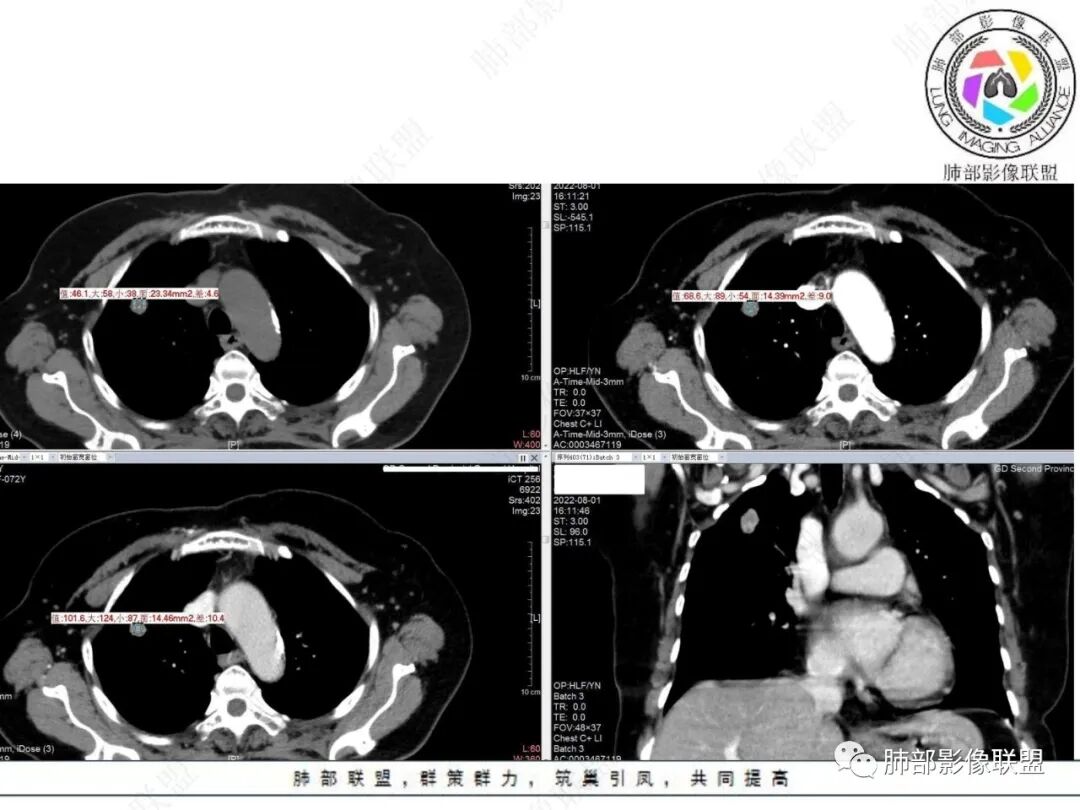

老年女性右肺上叶前段实性结节,边缘可见长短不一毛刺,临近胸膜受牵拉,中心疑似低密度影,空泡征?增强呈渐进性强化,首先考虑肺腺癌,鉴别良性肿瘤,错构瘤、PSP。

右肺上叶前段结节,边界清楚,可见浅分叶、毛刺、血管集束征及胸膜凹陷征,密度欠均匀,增强扫描渐进性明显强化,老年女性患者,体检发现,考虑腺癌,鉴别结核、慢性炎症。

右肺上叶结节,可见毛刺和血管集束征,老年女性患者,既往患病不详,首先考虑肺恶性肿瘤,腺癌可能性大,结合呕吐征象,建议完善外周检查,例如头颅磁共振排外脑转移。

右肺上叶前段结节,有分叶毛刺,胸膜牵拉不明显,毛刺细长比较软,密度不均中央有低密度坏死,呈明显环形延迟强化,考虑炎性肉芽肿,鉴别腺癌

右上肺结节边缘见毛刺,胸膜侧分叶,轻度强化,考虑恶性可能,腺癌,淋巴瘤样上皮癌,肉芽肿

右肺上叶结节看着就挺恶的,血管集束、冠状位看到一条血管弯曲,可疑空泡,周围似乎有磨玻璃?(需要薄层明确),这些征象支持腺癌。但是病灶比较明显的延迟强化、环形强化,毛刺比较长且收缩力不是太明显,炎性肉芽肿还是要考虑。

老年女性,正常肺背景,右肺上叶结节,边缘膨隆,浅分叶,长短毛刺,淋巴回流受阻,小空泡,显著强化,考虑肺腺癌,鉴别结核。

右肺上叶前段孤立性实性结节,不均匀明显延迟强化,形态不规则,位于胸膜侧见小锯齿状凸起,胸膜牵拉及兔耳侧,结节内上侧见磨破璃影,边清(需薄层确认),另见血进入结节,邻近血管集束征,结节外侧见指状凸起影(恶性多见),定恶性,腺Ca;鉴别炎性肉芽肿,结合肺肿瘤指标抗原检查,经皮肺穿刺活检!

右上叶结节,可见边缘清楚的GGO,可见分叶,胸膜牵拉线及长短不一的毛刺影,不均匀强化,坏死边界不清 ,72岁,高危病人,考虑浸润性腺癌

支持恶性结节,腺癌可能。右肺上叶尖段实性结节,边缘分叶、毛刺,与胸膜面数条牵拉线伴磨玻璃感(淋巴回流障碍),内隐约见支气管进入是否堵塞需要薄层重建。增强后静脉期中等强化。

右肺上叶实性结节,有分叶、长短不一毛刺,长毛刺较软,兔耳征但邻近胸膜无明显收缩,渐进性强化,中心密度低。考虑炎性肉芽肿,鉴别腺癌。

老年女性,虽有支持恶性的征象,但首先考虑炎性肉芽肿结节(结核?),原因:1.毛刺较长、较软,2.周围GGO不确切,3.增强后轻度延迟强化,内部见边缘较清楚的低密度相对不强化强化区。

老年女性,体检发现,无呼吸道症状。右肺上叶尖段孤立性实性结节,下份见空泡,余密度较均匀。病灶形态不规则,边缘多膨隆,可见浅分叶及细毛刺,血管集束,未能显示相关支气管情况。病灶胸膜侧见小锯齿状凸起、胸膜牵拉及兔耳征,结节前缘见磨玻璃影,磨玻璃影边界较清楚(需薄层确认),结节外侧见指状凸起影。未见卫星病灶,纵隔窗未见明显钙化。增强扫描:较明显渐进性强化。

2.病例分析:

老年女性,右肺上叶孤立实性结节,边缘欠光整,强化明显,未见卫星灶,已经让人高度警惕恶性肿瘤,尤其是腺癌!

浸润性腺癌支持点还有空泡及磨玻璃晕,但非薄层图像,磨玻璃影表现可靠性降低。

病灶张力不高,磨玻璃晕等需要鉴别隐球菌感染或其他炎性肉芽肿,虽然位置并不靠近胸膜。肺腺癌与隐球菌感染的鉴别,在影像学上也许是个永恒的话题。

没有卫星灶,没有树芽征,没有新旧不等,强化明显等不支持继发性肺结核。结节影边界欠光整,缺乏游离感,没有脂肪密度或钙化,强化特点等都未能显示出硬化性肺细胞瘤或者错构瘤的影像学特点。